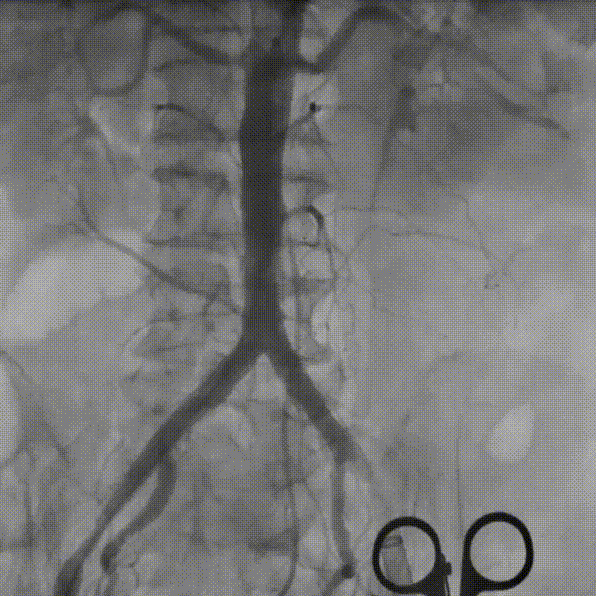

外周血管及主动脉弓解剖

双侧髂总动脉轻度扭曲少量钙化,腹主动脉折角明显,入路血管直径尚可,选择右侧为主入路,左侧为辅入路。

双侧髂总动脉轻度扭曲少量钙化,双侧髂外动脉内径细,左侧内径稍好,最细5.2mm,选择左侧为主入路,右侧为辅入路。

双侧髂主动脉轻度扭曲无钙化,双侧入路内径良好,选择右侧为主入路,左侧为辅入路。